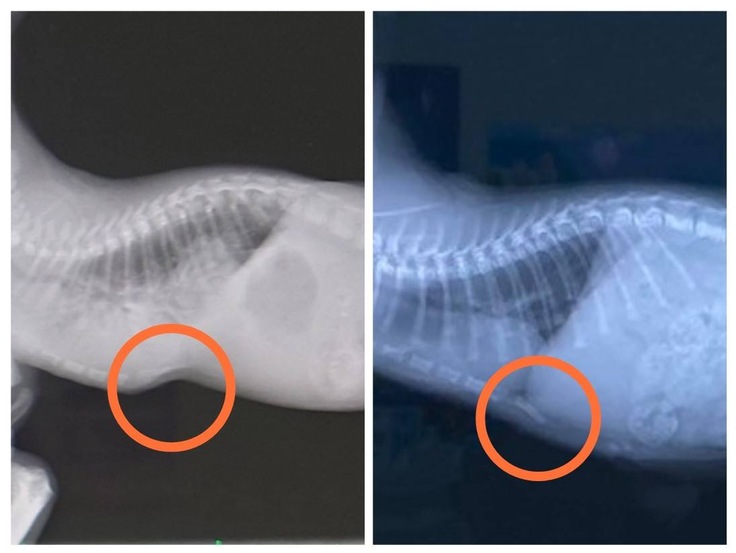

退院時(左)と現在(右)の肺のレントゲンを比べてみました。2匹ともまだ少しモヤはかかっていますが、だいぶ綺麗になりました。

ナイトの漏斗胸ですが、マッサージの甲斐もありほとんどわからないぐらいまで治りました。ただ一度歪んだ(凹んだ)骨は凹みがなくなっても少し外側に反ってしまっています。今のところ特に日常生活には問題はありません。今後もしっかり観察していこうと思います。

ヤマトはトイレをするときにおしっこは伏せの体制、うんちは高い声で唸る(叫ぶ)ことが気になっており相談してきました。特にレントゲンで異常は見当たらないようですが、うんちをするっと出やすくするために、療法食(消化器サポート)の話が出ました。様子を見て療法食を使用していくかもしれません。また変化がありましたら報告いたします。